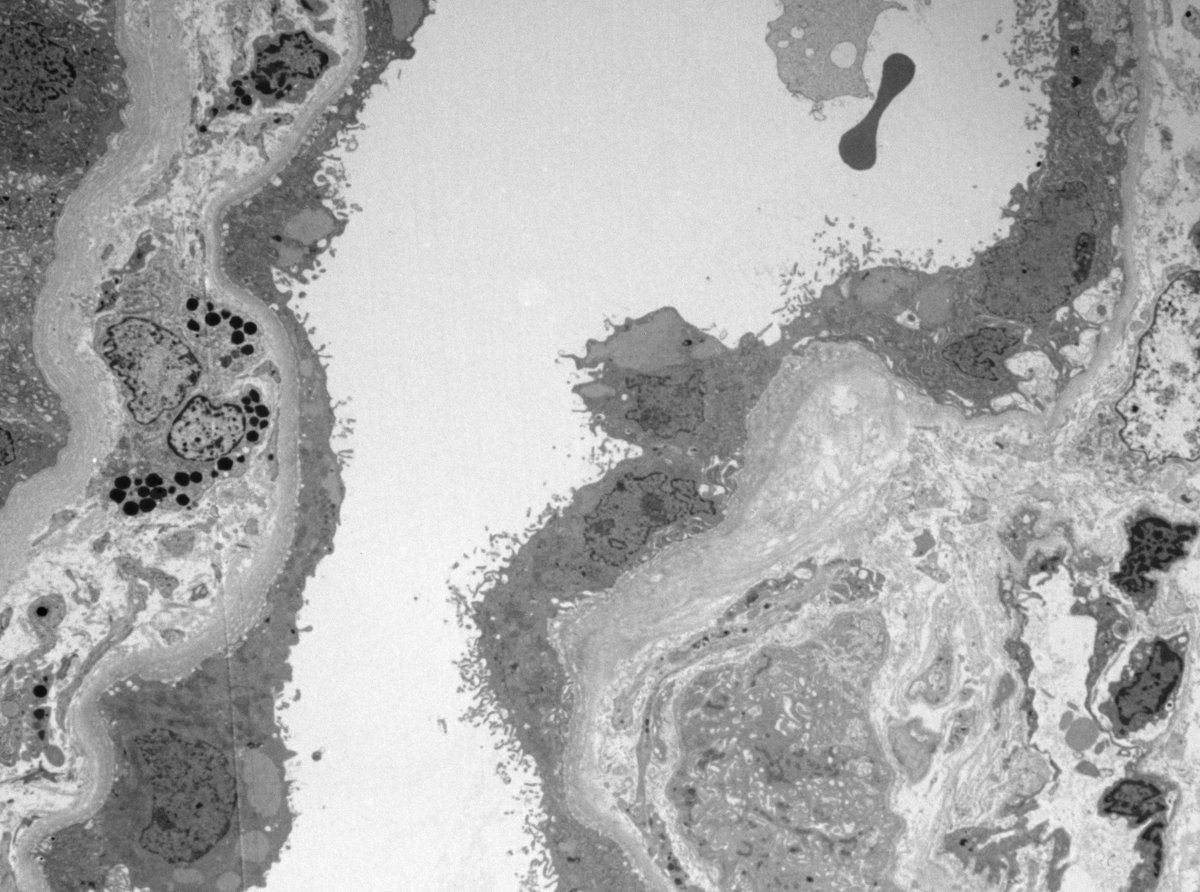

A patient presented to the emergency room with nausea, vomiting, abdominal pain, decreased urinary output, and rhabdomyolysis. History of heavy drinking and cocaine abuse. Below is his renal Bx @podocytes @koony84 @kelsmith_path @AlpersCharles @UWNephrology. DDx?